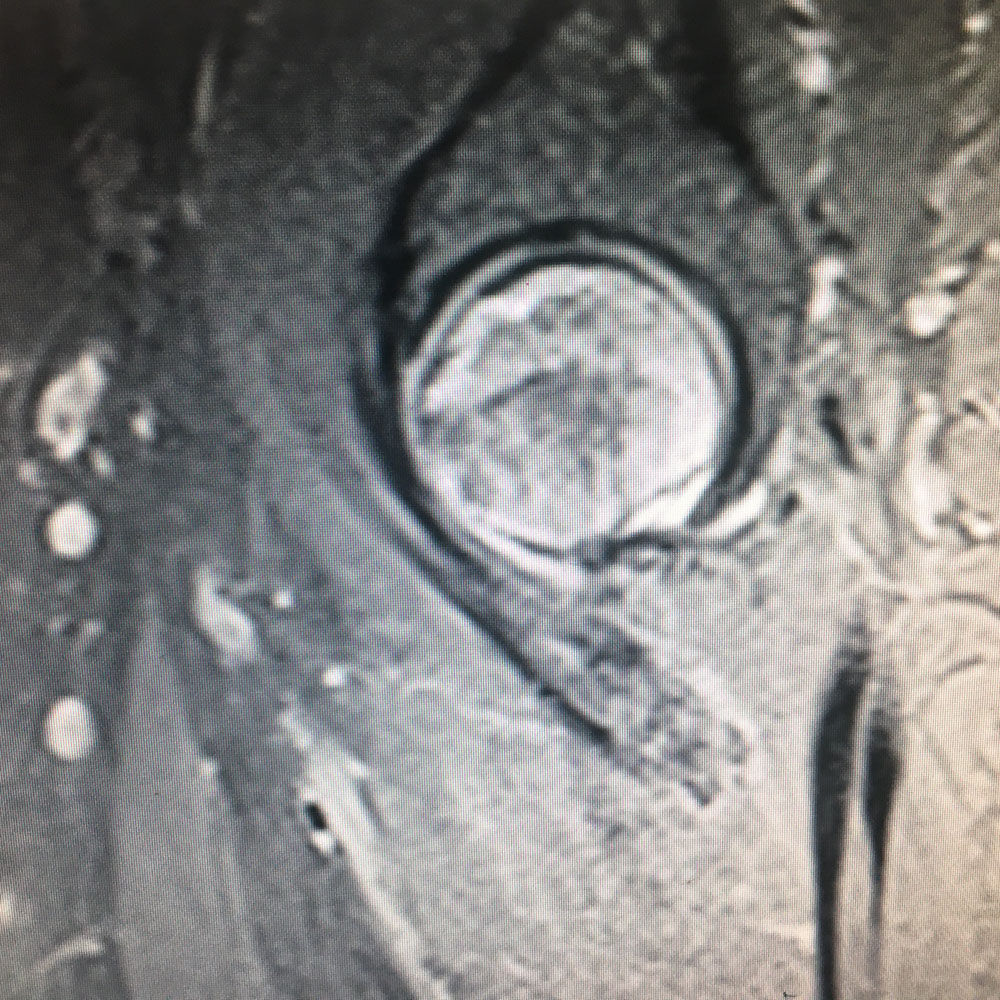

Εικόνα 2 (α,β): Αξονική Τομογραφία της δεξιάς κατ’ ισχίον άρθρωσης

Παρατηρούνται πολλαπλές εκφυλιστικές αλλοιώσεις σε αμφότερες τις κατ’ ισχίον αρθρώσεις, ενώ παρατηρείται κυστική αλλοίωση στη κεφαλή του δεξιού μηριαίου οστού. Ήπιες αλλοιώσεις ιερολαγονίτιδας δεξιά.